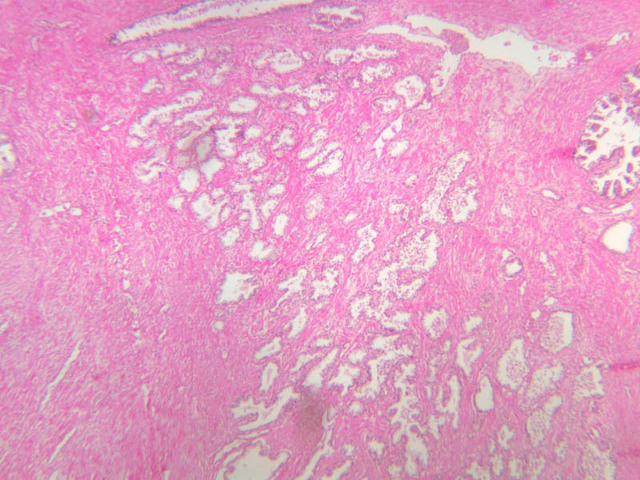

Scan a section of testis from the slide boxes at low magnification, and note the arrangement of the testicular components (slide B-80, H&E [1x-labeled, 1x, 1x]; B-81, PAS [1x, 1x]; B-82, adult monkey testis, H&E [1x, 1x, 1x, 1x, 1x] [2.5x, 10x]). A thick fibroelastic connective tissue capsule, or tunica albuginea, surrounds the testis. Within the tunica and sometimes bulging inward are a number of large blood vessels. The larger, thicker walled vascular profiles are sections through the testicular artery, which executes a highly convoluted course through the tunical plane. Closely applied to the outer surface of the tunica albuginea is the visceral layer of the tunica vaginalis, whose free surface is lined with mesothelium (B-81, PAS [2.5x-labeled]). In some specimens the parietal layer of the tunica vaginalis has been removed, but in others it is possible to find both layers of the tunica vaginalis and the potential serous space between them. How does the tunica vaginalis originate? Connective tissue septa extend inward from the tunica albuginea, subdividing the testis into a number of lobules. Within each lobule are numerous profiles of seminiferous tubules (B-82 [2.5x-labeled, 10x] [20x, 40x]). The interstitial space between the seminiferous tubules is occupied by a loose connective tissue matrix that is permeated by blood and lymphatic vessels and contains clusters of Leydig cells (interstitial cells) (B-82 [40x-labeled]).

The prostate is an aggregate of numerous tubulo-alveolar glands embedded in a dense stroma of collagen fibers and smooth muscle (B-90 [2.5x, 10x, 20x, 40x-labeled]; B-91 [2.5x, 10x, [[http://www.medicalhistology.us/wiki/bin/viewfile/Main/ProstateImages?rev=1;filename=b91_prostate_adult_20x_he.jpg[20x]], 40x-labeled] [2.5x, 10x, 10x, 20x, 40x]). Note that the prostatic urethra, the portion of the urethra which runs through the prostate gland, is also present (B-91 [2.5x, 10x, 20x, 40x]). Under high dry magnification, it is obvious that the glandular epithelium varies from simple cuboidal to pseudostratified columnar. Prostatic acini often contain eosinophilic corpora amalacea (prostatic concretions) (B-90 [2.5x, 10x, 20x, 40x-labeled]). The number and degree of calcification of these spherical, lamellated structures increase with age. In some sections, the prostatic urethra can be identified. Functional, as well as morphological, maintenance of the adult prostate and seminal vesicles depends on adequate levels of circulating testosterone. Examine the prepubertal prostate (B-92 [2.5x, 10x, 20x, 40x] [2.5x-labeled, 10x, 20x, 40x]). How does this specimen differ from that on slide B-90?